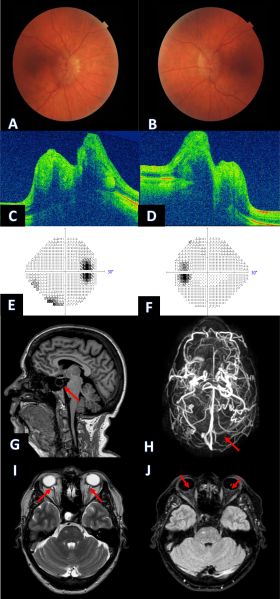

A 65-year-old woman presented with a case of IIH displaying symptoms of chronic headaches, transient visual loss upon postural changes (typically lasting seconds), and pulsatile tinnitus. Examinations revealed several key findings: bilateral papilledema (A and B), evident optic nerve head swelling in an OCT cross-section, notably more pronounced swelling in the nasal borders (C and D), an enlarged blind spot observed in the visual field (E and F), and an empty sella seen in the sagittal view of MRI (G). Additionally, MRA/MRV showcased the absence of signal in the right transverse vein sinus (H), contrasting with a clear signal in the left side (highlighted by a red arrow). Further observations included enhancement (with gadolinium) of the prelaminar optic nerve, distension of the perioptic subarachnoid space, and tortuosity of the orbital optic nerve (I), along with intraocular protrusion of the prelaminar optic nerve (J). (Image courtesy of J. Khadamy)